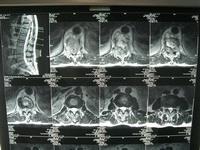

根据病史、体征和X线摄片表现,必要时辅以CT可作出诊断。但是,早期病例,椎旁无脓肿和窦道,其它部位无结核病变者,诊断较为困难。

1.X线摄片 脊椎X线正位摄片必要时也可照斜位片表现分别说明如下:

(1)椎弓根病变 椎体上部棘突上方两侧圆形椭圆形影像,不对称的溶骨性破坏模糊不清者。

(2)椎板病变 棘突两旁骨质密度低。

(3)棘突病变:与上下正常棘突比较原有棘突部分或全部阴影消失者。